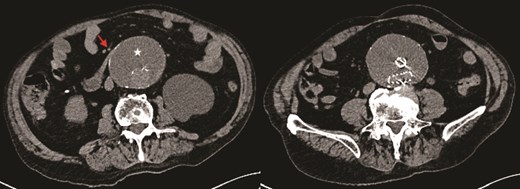

He presented with acute-onset abdominal pain, profuse vomiting, and diarrhea that began 1 day prior to admission. A contrast-enhanced CT scan revealed duodenal obstruction due to extrinsic compression by the aneurysmal sac, now measuring 9 cm in anteroposterior diameter, particularly at the level of the third portion of the duodenum (Figs 1 and 2). There was no evidence of endoleak. Incidentally, the scan also identified a suspicious rectal lesion. Laboratory investigations showed acute-on-chronic kidney injury with significant electrolyte disturbances. Initial management included nasogastric decompression, which yielded 3000 ml of gastric contents, along with fluid resuscitation, correction of metabolic derangements, and initiation of total parenteral nutrition. A multidisciplinary discussion was held involving vascular, general, and upper GI surgical teams. Surgical options, including a gastrojejunostomy to relieve the obstruction, were discussed in detail with the patient. After thorough deliberation, the patient declined any surgical intervention and opted for exclusive palliative care. He also refused further investigation of the rectal lesion. The clinical course was notable for symptomatic improvement within 48 hours, allowing for the gradual reintroduction of oral intake. The patient was subsequently discharged to a peripheral rehabilitation facility for continued supportive care.

Axial CT image demonstrating obstruction of the duodenum at D3 between the aortic sac (star) and superior mesenteric artery (SMA) (arrow).